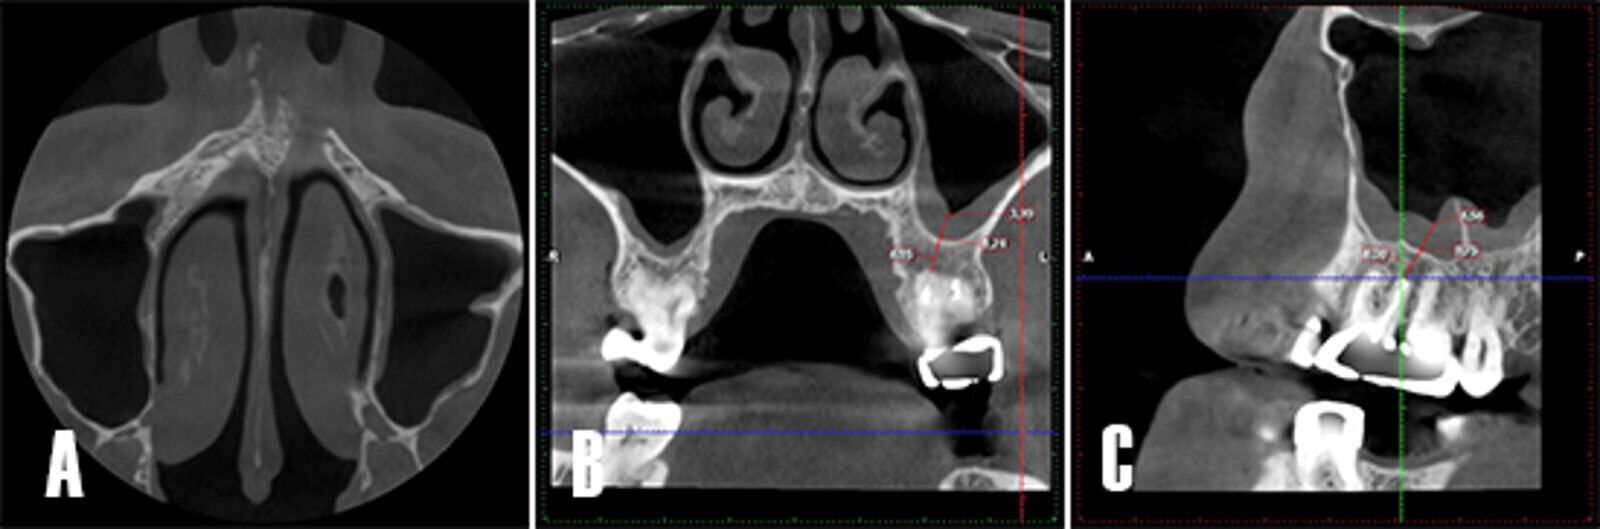

Control tomográfico a los 12 meses. A) Corte en el plano axial: se observa la cavidad sinusal sin opacificación. B) Corte coronal: se observa la cavidad sinusal limpia, la zona apical se observa más radiodensa, lo que sugiere la formación de hueso nuevo. C) Corte sagital: se aprecia cómo el engrosamiento de la membrana se asocia a la presencia del septo óseo del seno maxilar.

Figura 8. Control tomográfico a los 12 meses. A) Corte en el plano axial: se observa la cavidad sinusal sin opacificación. B) Corte coronal: se observa la cavidad sinusal limpia, la zona apical se observa más radiodensa, lo que sugiere la formación de hueso nuevo. C) Corte sagital: se aprecia cómo el engrosamiento de la membrana se asocia a la presencia del septo óseo del seno maxilar.

La sutura se removió una semana después de la cirugía. Se pudo observar como la tumefacción de los tejidos blandos remitió (Fig. 7A). El paciente fue citado 4 semanas tras la cirugía para monitorizar la sintomatología clínica y evaluar la zona tratada (Fig. 7B). A los 12 meses se reevaluó el caso (Fig. 7C) y se realizó una TCHC para valorar el seno maxilar afectado, se pudo observar como la cicatrización de la periodontitis apical y la patología sinusal remitieron (Fig. 8).